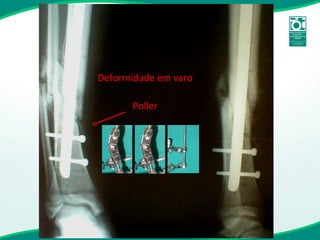

Fixador monoaxial de tíbia conversão

Deformidade em varo Poller

Erro no ponto de entrada Ponto de entrada muito medial